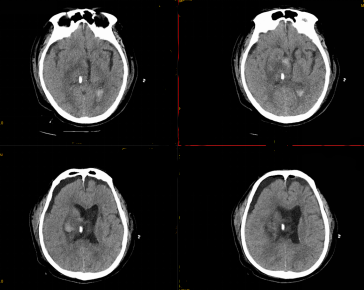

2020-10-19凌晨00时周某头晕头痛,伴大汗淋漓恶心、呕吐,由家属送至我院急诊就诊,就诊意识逐渐模糊,到我院急诊科时已昏迷,呼之不应,急诊头颅CT提示:右侧丘脑基底节区出血并破入脑室。神经外科医生检查发现患者深度昏迷、瞳孔散大、呼吸困难当即决定紧急行神经导航下显微手术治疗,手术仅2小时即顺利完成,术后复查见血肿完全清除,第二天患者即部分恢复意识。现患者恢复清醒,正结合中医、壮医康复之中。

手术在我院神经外科蔡利主任带领下,利用神经导航进行精确规划,精准定位血肿与周围神经结构,合理设计手术切口,显微镜下锁孔开颅,利用纵裂这一大脑自然间隙,最大化减少医源性创伤,完全清除了血肿,同时保护了血肿周围的重要神经结构。

经蔡利主任介绍,丘脑出血位置深、毗邻众多重要神经、血管结构,手术难度高、风险大,保守治疗是以往临床常用的治疗丘脑出血的方法,但疗效并不理想。患者血肿破入脑室且出血量超过15ml时,治疗方式多为血肿穿刺术与侧脑室引流术相结合,并在术后间断注射尿激酶液化引流血肿,不过,此种治疗方法无法将血肿压迫下丘脑及脑干的情况在短时间解除,因而效果也不理想。微创手术是近几年临床上广泛采用的治疗丘脑出血的方法,具有创伤小、出血量少、手术时间短等优势,得到医生及患者的认可。显微镜下锁孔手术充分践行了微创手术理念,在显微镜下借助神经导航,医生可精确地定位出血位置,保证手术视野良好,同时,通过内镜或显微镜光源的转变,能够清楚地显示微小血管,使止血操作有效进行。